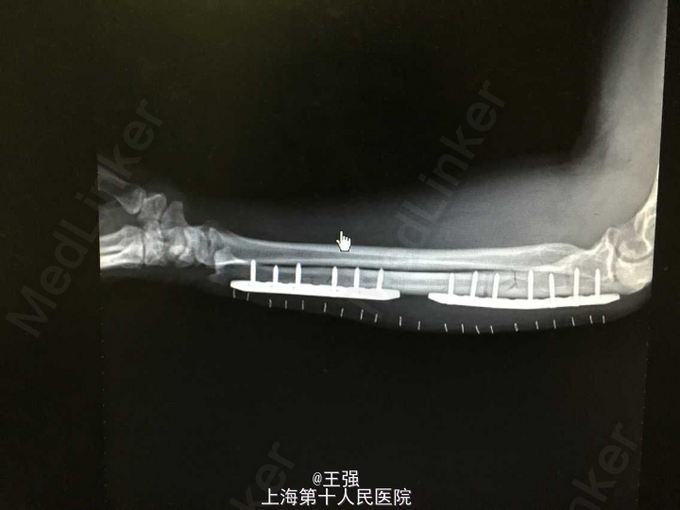

诊断:1.尺骨骨折(左,近端及远端) 2.高血压 治疗:入院后完善相关检查,控制血压,排除手术禁忌症后行骨折切开内固定术,术顺,术后予以抗炎、补液及对症治疗。

随访讨论:患者出院时一般情况可,无发热,心肺听诊无殊,患肢伤口愈合好,无肿胀及渗出,患肢血运感觉可,嘱一个月后门诊复查。